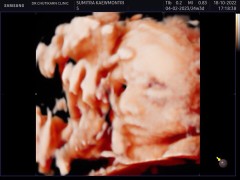

มาโชว์รูปซาว 4 มิติกันหน่อยค่าแม่ๆ คลอดจริงมาคล้ายในภาพไหมคะ

บ้านนี้เพิ่งไปซาว 4 มิติมาตอนอายุครรภ์ 28week ค่ะ